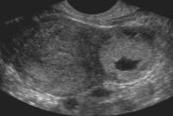

- Interstitial portion of fallopian tube – suggested by gestational sac with <5mm of surrounding myometrium (Illustration 13)

- Illustration 13. Transvaginal ultrasound in a transverse plane showing an interstitial pregnancy.